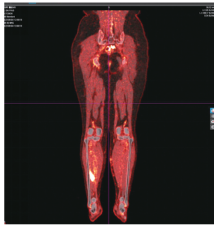

宫颈癌肌间转移不常见,小腿肌间转移尤为罕见。现报道1例宫颈癌小腿肌间转移病例。目前针对远处肌间转移的宫颈癌治疗虽无统一的治疗标准,但仍以多学科会诊为主,争取给患者获得更多的治疗选择和生存机会,使患者获益最大化。